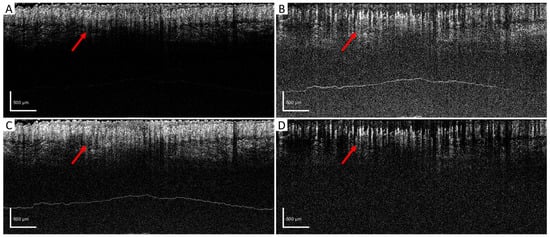

For further evaluation, en face results were generated by using maximum intensity projection (MIP) within the papillary dermis layers, which contained dense and small blood vessels when observing the pre-acquired data. In order to compare the algorithms quantitatively, a ground truth is desired. However, one is not available for in vivo studies. Therefore, we utilized a four-time registration result as the alternative ground truth. Four successive acquisitions at the same scanning location were processed by aED, then registered into one 3D dataset using the Elastix registration toolbox [45,46]. The four-time registration result would contain low noise and low motion artifacts, even though it had taken a long acquisition time. Hence, the four-time registration result was used as the reference image when calculating the PSNR values. In Figure 5, the same MIP processing was applied to all processed blood-flow datasets from (A) four-time registration, (B) SV, (C) aED, (D) bED, and (E) wED. For each processing method, three regions were enlarged to observe the algorithms’ performance more clearly. Additionally, to present wED’s consistent performance, two alternative datasets from different stages of wound healing were processed to generate the same comparisons with that in Figure 5, which are presented in Appendix A Figure A1 and Figure A2.

Figure 5. The comparisons of en face results from maximum intensity projection using different algorithms. (A) Registration from 4-time acquisitions; (B) SV; (C) aED; (D) bED; (E) wED. (All scale bars represent 500 μm); SV: Speckle Variance; aED: A-scan eigen-decomposition; bED: B-scan eigen-decomposition; wED: windowed eigen-decomposition.

In Figure 5, the en face and quantitative comparisons among four-time registration, SV, aED, bED, and wED are shown. With the four-time registration result as the ground truth, the PSNR was calculated for each algorithm to be evaluated (shown in Figure 5). The proposed wED had the highest PSNR value, 12.01, while the second highest is from aED, 11.48, which indicates the proposed approach wED has improved the reconstruction performance by 4.6%. Note that sometimes the aED results could have a higher PSNR when wED results were visually better, because the four-time registration result was not a perfect ground truth. Due to its long acquisition time (four times of a normal OCTA scan), the four-time registration result could have transformations (moving, translation, rigid, affine, and B-spline) of the vessel structure. As a result, the aED with higher background intensity could have a higher PSNR value instead. Visual judgment in Figure 5 could also match the quantitative results. To demonstrate the detailed visual difference among these algorithms, three areas in all en face results were enlarged as green, yellow, and red regions. SV could hardly resolve any blood-flow signals due to high motion effects. Although bED had some blood signals underneath the horizontal motion artifacts, these artifacts were too many to present any vessel networks. Matching with the B-scan comparison, only aED and wED were able to resolve most of the blood-flow signals. For the green region, wED could still generate less background noise, which provided better contrast of the blood vessels. Within the yellow region, a breathing motion artifact occurred. The bright horizontal lines could be observed in the aED result. In the wED result, while the breathing artifact did not disappear, it was reduced compared to the aED. In the red region, wED had better contrast of small vessels compared to aED. In addition, some motion artifacts still existed in the aED result, while they could hardly be seen from wED.

Figure A1. The comparisons of en face results from maximum intensity projection. (A) Registration from 4-time acquisitions; (B) SV; (C) aED; (D) bED; (E) wED. (All scale bars represent 500 μm); SV: Speckle Variance; aED: A-scan eigen-decomposition; bED: B-scan eigen-decomposition; wED: windowed eigen-decomposition.

Figure A2. The comparisons of en face results from maximum intensity projection using different algorithms. (A) Registration from 4-time acquisitions; (B) SV; (C) aED; (D) bED; (E) wED. (All scale bars represent 500 μm); SV: Speckle Variance; aED: A-scan eigen-decomposition; bED: B-scan eigen-decomposition; wED: windowed eigen-decomposition.